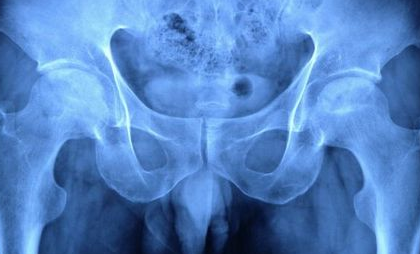

从股骨头坏死早期症状图中可以看出哪些早期股骨头坏

河南股骨头坏死医院介绍股骨头坏死为常见的骨关节病之一。若不及时治疗可能会导致关节的受…[详情]

郑州股骨头坏死骨科医院讲解股骨头坏死是怎么回事?

郑州股骨头坏死骨科医院介绍到在临床中,由于股骨头的血运比较差,通常靠的还是旋股外侧动…[详情]